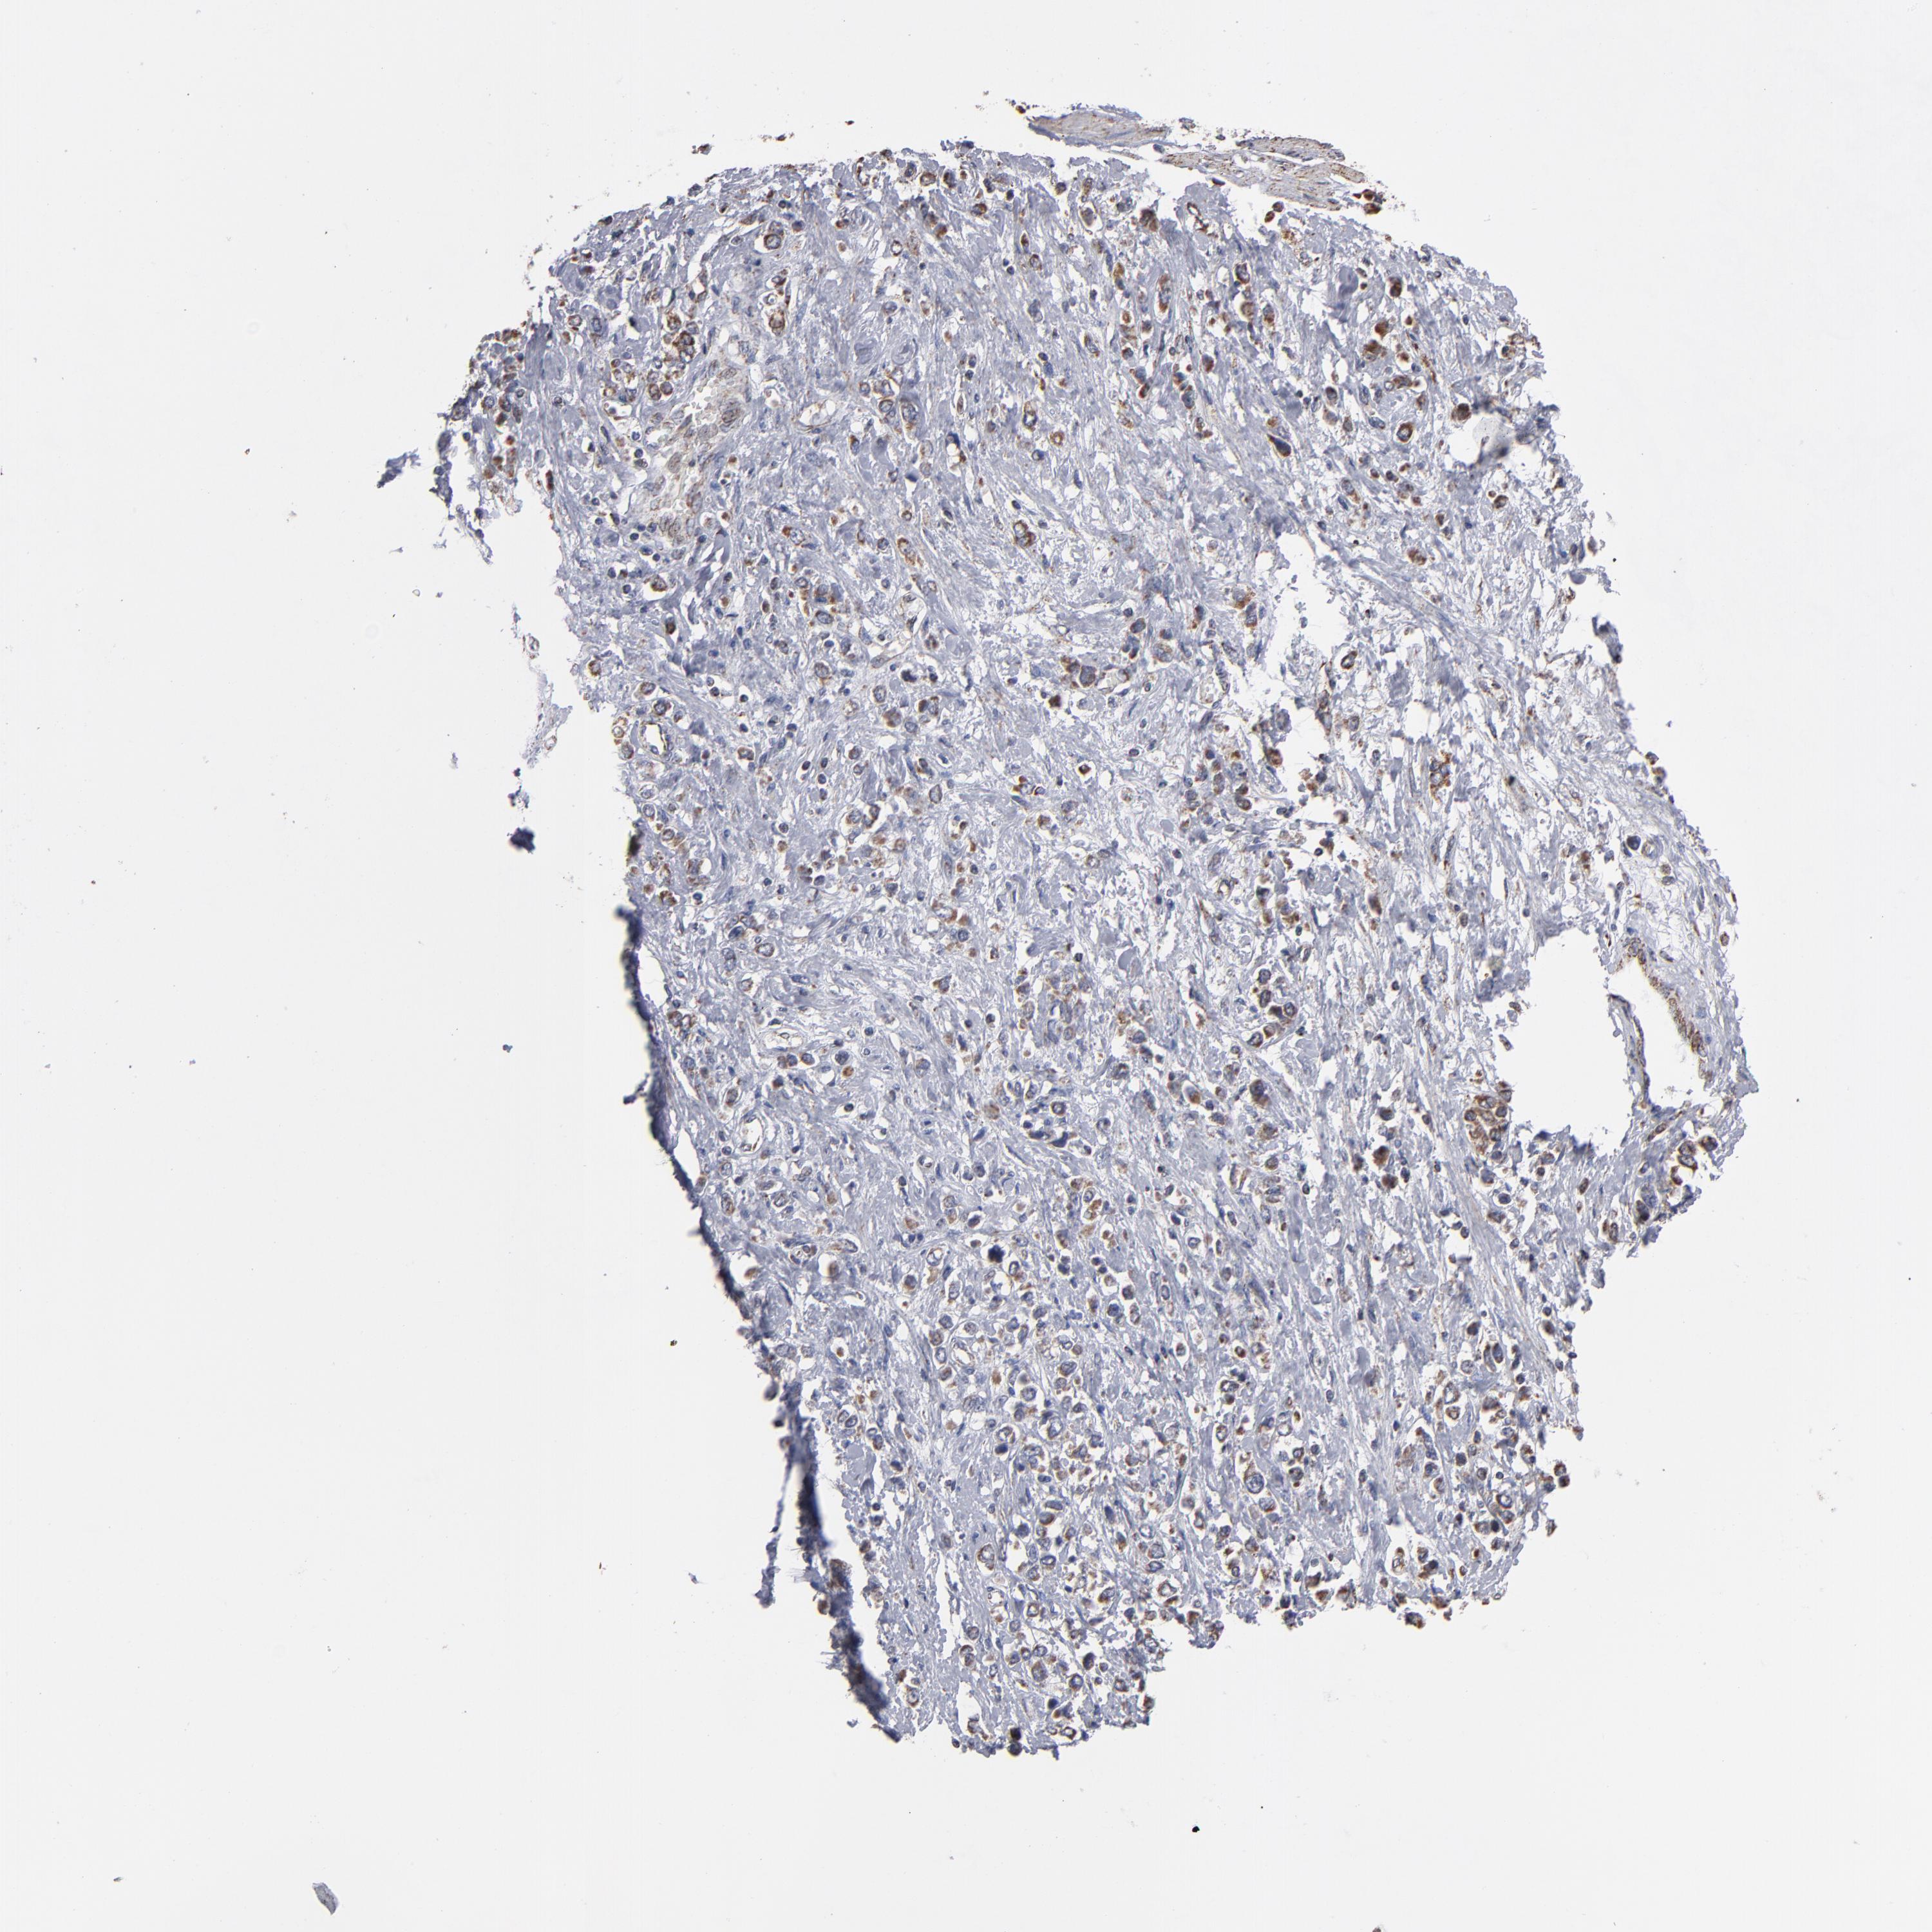

STOMACH CANCER - Protein expressioni

A mouse-over function shows sample information and annotation data. Click on an image to view it in a full screen mode. Samples can be filtered based on level of antibody staining by selecting one or several of the following categories: high, medium, low and not detected. The assay and annotation is described here.

Note that samples used for immunohistochemistry by the Human Protein Atlas do not correspond to samples in the TCGA dataset.

Antibody stainingi

Antibody staining in the annotated cell types in the current human tissue is reported as not detected, low, medium, or high, based on conventional immunohistochemistry profiling in selected tissues. This score is based on the combination of the staining intensity and fraction of stained cells.

Each image is clickable and will lead to virtual microscopy that enables deeper exploration of all samples and also displays staining intensity scores, fraction scores and subcellular localization as well as patient and tissue information for each sample.

Antibody HPA002893

Staining

High

Medium

Low

Not detected

Intensity

Strong

Moderate

Weak

Negative

Quantity

>75%

75%-25%

<25%

None

Location

Nuclear

Cytoplasmic/membranous

Cytoplasmic/membranous,nuclear

Adenocarcinoma, NOS